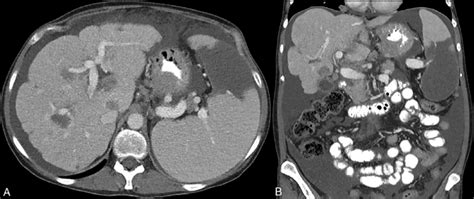

So, what exactly causes this tricky condition we call pseudocirrhosis today ? It’s not one single thing, but rather a collection of different scenarios that can lead to this nodular appearance of the liver. One of the most common culprits is Budd-Chiari syndrome , especially when it’s chronic. Think of this as a blockage in the veins that drain blood from the liver. When blood can’t get out efficiently, the liver can become congested, leading to changes that can look like pseudocirrhosis on imaging. Another significant cause is hepatic vein obstruction from other reasons, like clots or external compression. We also see it in conditions involving portal hypertension , where the pressure in the portal vein (which brings blood to the liver) is abnormally high. This can happen due to problems before the blood reaches the liver, like spleen enlargement, or within the liver itself, even if it’s not true cirrhosis. Certain types of infiltrative diseases , such as some cancers that spread to the liver (metastases) or rare conditions like sarcoidosis, can also create a nodular pattern that mimics cirrhosis. Even severe fatty liver disease in some cases, when it’s really advanced and causes significant inflammation and scarring in localized areas, might present with features that can be confused with pseudocirrhosis. The diagnostic journey to figure out pseudocirrhosis involves a combination of tools. Imaging studies like ultrasounds, CT scans, and MRIs are usually the first step. They can show the nodular texture of the liver. However, imaging alone isn’t always definitive because, as we’ve discussed, it can resemble true cirrhosis. That’s where blood tests come in. Doctors will look at liver function tests, but they also need to investigate the cause . For example, if Budd-Chiari syndrome is suspected, tests might involve looking for blood clotting disorders. If infiltration is a concern, tumor markers or specific blood tests for inflammatory conditions might be ordered. Ultimately, a liver biopsy is often the gold standard for a definitive diagnosis. A small piece of liver tissue is examined under a microscope. This allows pathologists to see the specific changes, confirm the absence of widespread fibrosis of true cirrhosis, and identify any underlying cellular abnormalities or infiltrates that point to the correct cause. This detailed examination is crucial for differentiating pseudocirrhosis from true cirrhosis and guiding the appropriate treatment. The key takeaway here is that this nodular appearance is a sign , not a disease in itself, and finding that underlying cause is paramount.